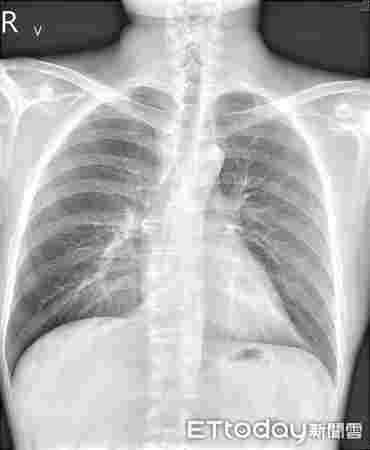

臺灣媒體最近報道了一個“令人震驚”的案例,一名30歲的男子據稱對電子煙產生了極端過敏反應,導致他出現了嚴重的呼吸道皮膚病癥狀。

在短短幾個月的時間里,該男子開始出現咳嗽、氣喘、痰多、呼吸困難等呼吸道癥狀,以及全身皮膚干燥瘙癢的嚴重過敏反應。 他最近因懷疑電子香煙引起過敏反應而住進臺北一家醫院。

治療這名電子煙用戶的蘇一峰醫生告訴記者,該患者在開始吸電子煙之前,頭部出現了局部牛皮癬,但在開始吸電子煙后,癥狀惡化,最終全身出現了嚴重的牛皮癬。

但皮膚病只是問題的一部分,這位臺灣醫生補充說,他的病人還患有哮喘,被診斷為肺炎,他的血液檢查也顯示他的過敏指數飆升。 聽他這么說,都是因為那些討厭的電子煙。